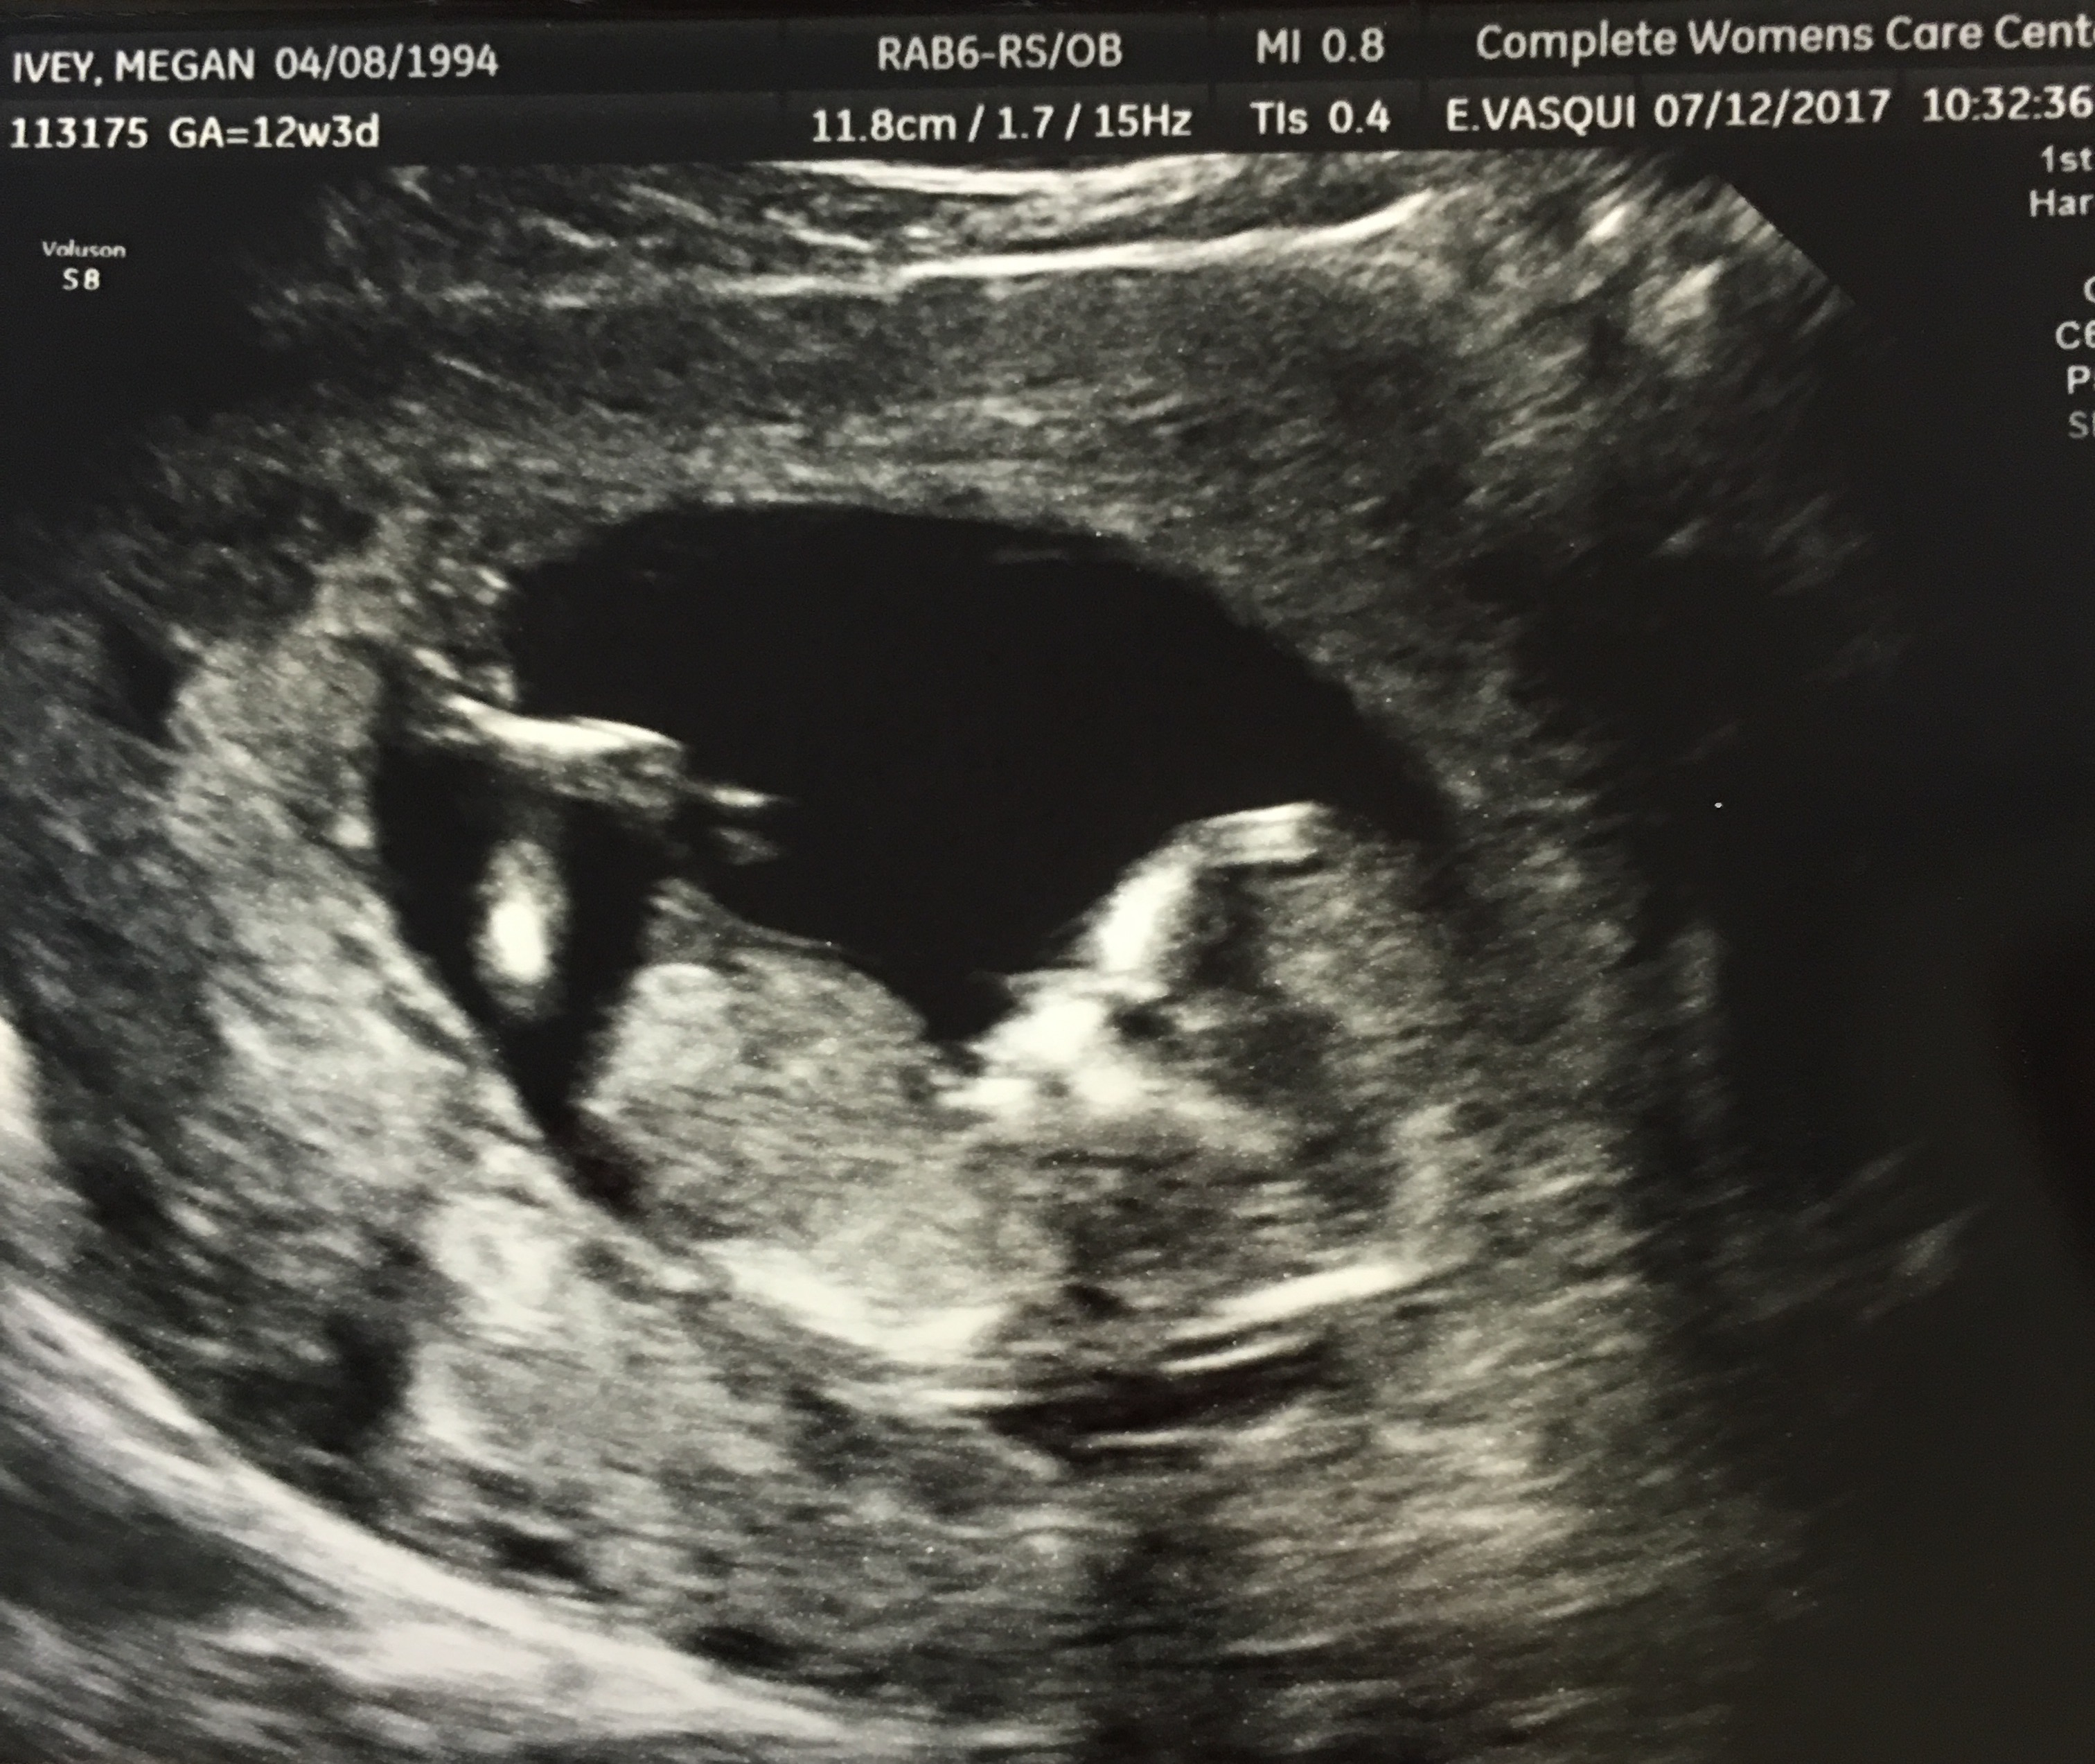

12w3d NT Scan- possible boy?

Went for my Nt scan today & nurse took a guess for a boy! I wish I had gotten the better views that she did show me, but I was too caught in the moment. The last picture (horrible quality, I know) was a screenshot of the video on my phone.

I know there's many theories such as the nub theory, skull theory, & ramzi's theory- being a first time mom, I have no clue what I'm looking for! Thoughts on gender? 🤗

Attachment 37042Attachment 37043Attachment 37044